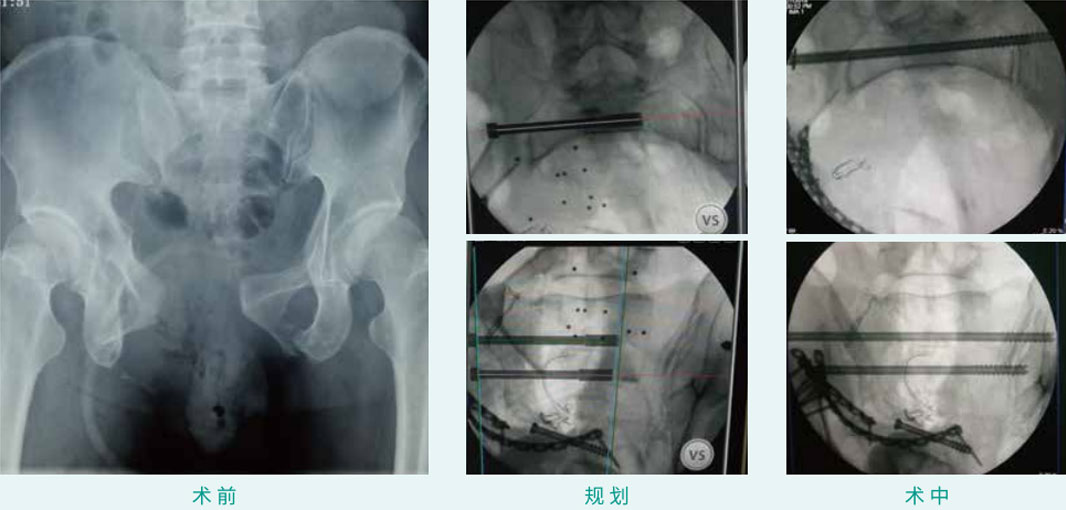

天玑? 辅助骶髂螺钉(骶1、骶2)经皮空心螺钉内牢靠术

基本情形:患者男,27岁,骨盆骨折

机械人累积用时:15分钟

植入物:2枚空心螺钉

病例泉源:中国人民解放军总医院(301医院) 陈华